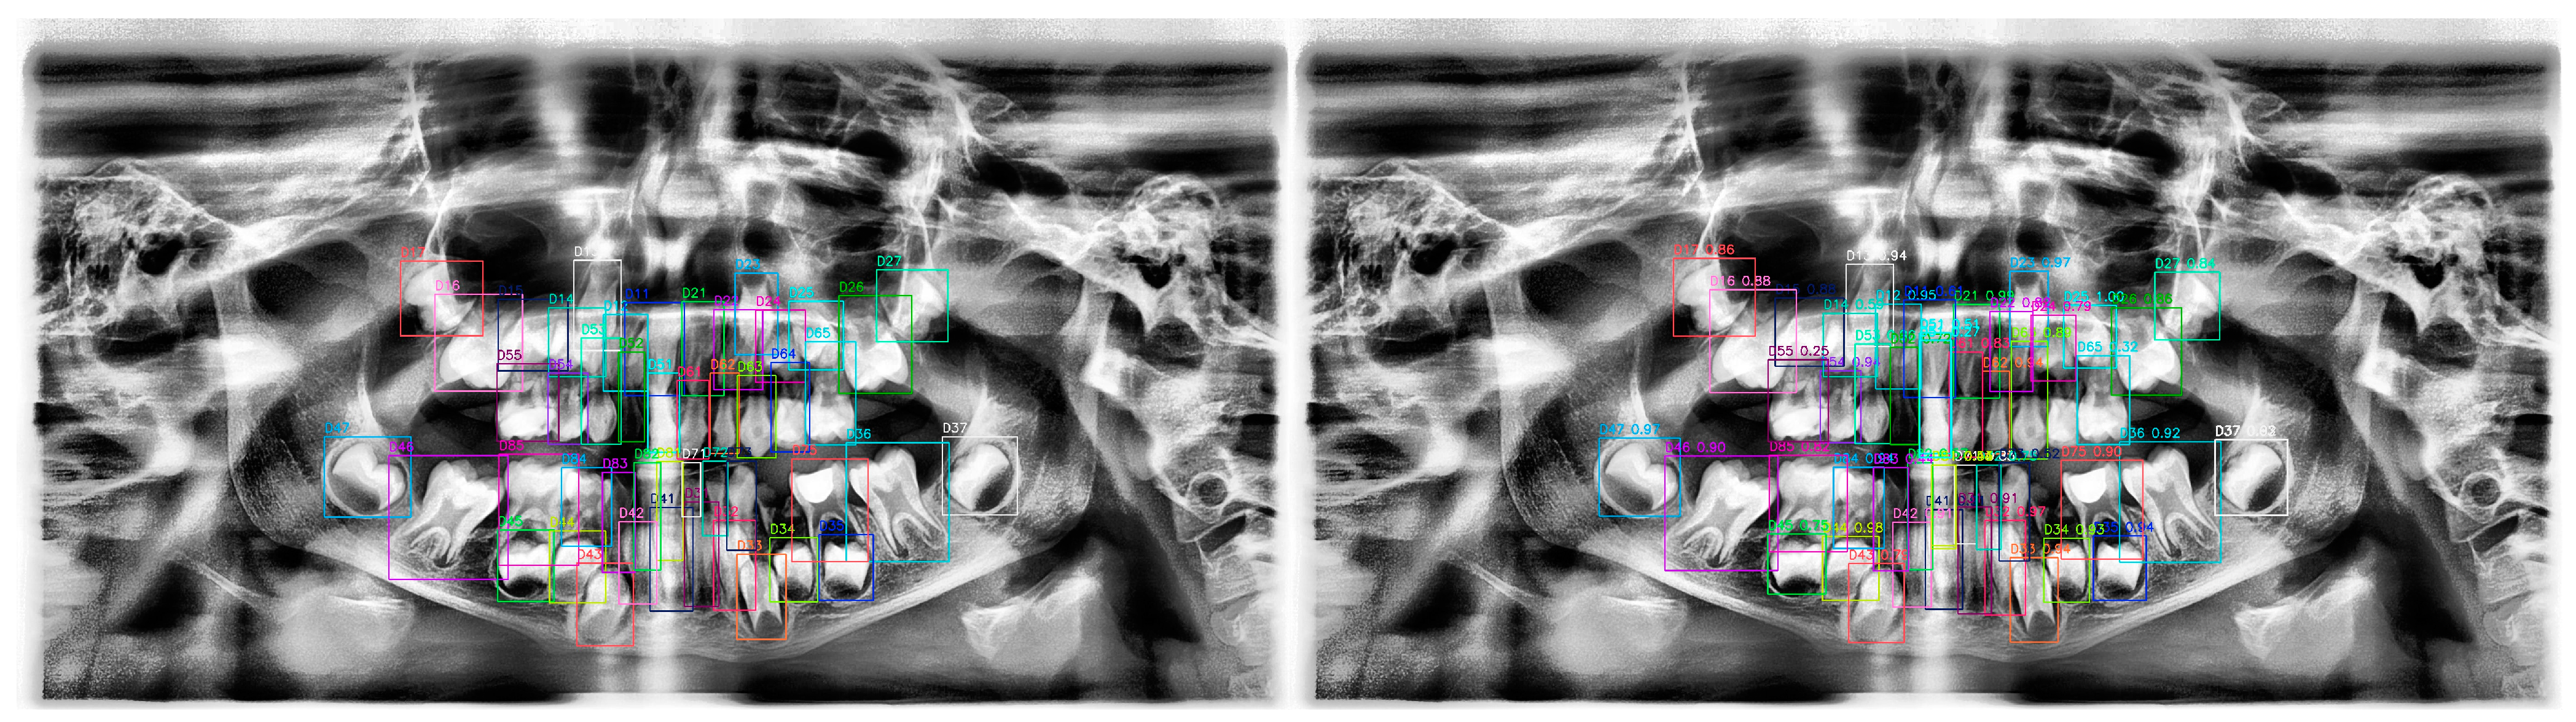

Evaluation of the Performance of a YOLOv10-Based Deep Learning Model for Tooth Detection and Numbering on Panoramic Radiographs of Patients in the Mixed Dentition Period

2.4. Ground Truth Labeling